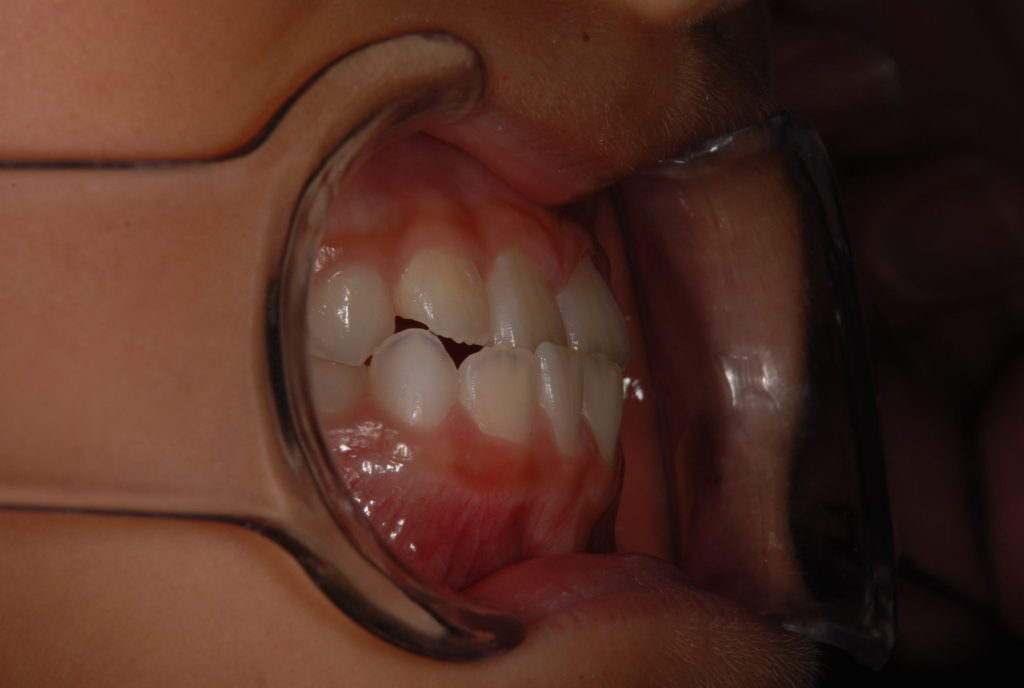

子供の矯正 前歯の反対咬合 7歳

7歳 男の子前歯が1本だけ反対にかみ合ってしまっています。乳歯の生えかわりがうまくいかない時に起きやすいのですが、放っておくと歯だけでなく それを支える上あごの成長を阻害してしまう恐れがあるので早期に噛みあわせを正くしてあげてあ...

子供の矯正 乳歯の反対咬合5歳

5歳 男の子 まだ永久歯が生える前の乳歯列の段階で 反対咬合です。奥歯で噛みあわすと前歯が邪魔して、下あごを前にずらして噛んでいました。 早いうちに前歯の噛み合わせを正す事、年齢的に取り外せる装置...

子供の矯正 反対咬合8歳

8歳 女の子上下4本ずつ永久歯に生え変わって、反対咬合になっていました。 実際はもっと下あごを引っ込められるが、咬み合わすと前歯が邪魔して下あごが前方にスライドして余計に受け口になってしまう状態です...